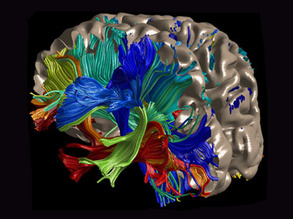

White Matters